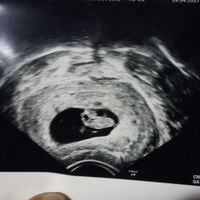

4Qualcuna che se ne intende? Io di angoli non ho capito nulla provate a indovinare , forse il 23 agosto riuscirò a vedere il sesso e vi dirò se avete indovinato!!! !

Ragazze sono di 7 settimane oggi ed ho appena fatto l'ecografia, si capisce cosa potrebbe essere in base al metodo Ramzi? 😊😊 Ho già un maschietto di 2 anni

Oggi ho fatto il Gtest e tra dieci giorni circa oltre agli altri esami avrò il risultato anche del sesso, così un po’ per divertirci a sfatare miti volevo allegare 2 ecografie una di 8 settimane fatta...